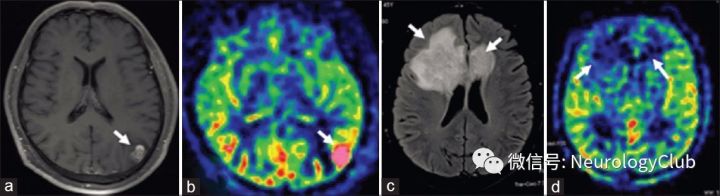

根据神经影像学形态特征,可以将TDLs的病灶分为三类(图1-7):(1)弥漫浸润性病灶:边界不清,不均匀强化,T2WI可见弥漫浸润性生长方式(图1a和b);(2)环形强化病灶:病灶为圆形或类圆形,呈闭环或开环强化(图1c);(3)巨大囊性病灶:T1WI低信号,T2WI高信号,边界清,环形强化(图1d)。

图1:三例TDLs患者,三种形态类型:浸润性(a和b),环形强化(c)和巨大囊性(d)

PWI可用于TDLs和脑肿瘤的鉴别。高灌注通常见于胶质瘤(图7a和b),而TDLs灌注多不增高(图7c和d)。